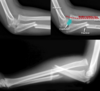

**Colles - ‘dinner fork type deformity’** Features of the injury 1. Transverse fracture of the radius 2. 1 inch proximal to the radio-carpal joint 3. Dorsal displacement and angulation of the distal radius

**Smith's fracture (reverse Colles' fracture)** 1. Volar angulation of distal radius fragment (Garden spade deformity) 2. Caused by falling backwards onto the palm of an outstretched hand or falling with wrists flexed

Colles vs Smith fracture

Colles fracture ## Footnote Typically FOOSH forwards Extra-articular radial # with dorsal (posterior / back of hand) angulation and displacement

Smith Fracture ## Footnote Typically FOOSH back of hand Extra-articular radial # with volar (anterior / palmar) angulation and displacement